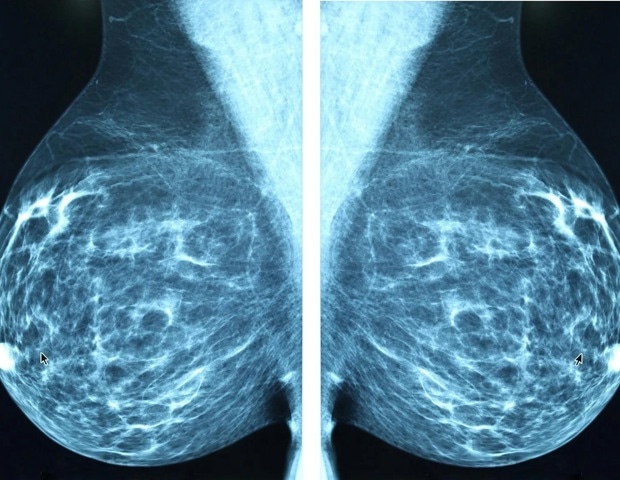

L’Alliance mondiale ABC a lancé aujourd’hui le Rapport mondial sur la décennie 2015-2025 concernant le cancer du sein avancé (ABC), une évaluation mondiale historique révélant une décennie de progrès scientifiques remarquables qui ont transformé les soins ABC pour certaines patientes dans certains pays, alors que de nombreux autres dans le monde n’en ont pas encore bénéficié.

Les résultats révèlent des inégalités profondes et persistantes qui laissent de nombreux patients de côté. Le thème central du rapport, « La connaissance en mouvement », souligne le besoin urgent de traduire une décennie de données probantes et d’innovation en actions qui changent la vie de chaque personne vivant avec l’ABC.

- L’hypothèse selon laquelle l’ABC est une condamnation à mort rapide et que l’argent dépensé pour le traiter est gaspillé s’est avérée fausse. Le taux de survie global médian sur cinq ans des femmes atteintes d’ABC est passé à 33 %, contre 26 % il y a dix ans, avec des données réelles montrant une survie médiane pour la maladie HER2+ dépassant 50 mois dans certaines régions.

- La survie globale médiane pour ABC triple négatif a augmenté de moins de trois mois au cours de la dernière décennie, restant à seulement 13 mois.

- Les disparités dans l’accès aux thérapies biologiques ou ciblées persistent à l’échelle mondiale, des médicaments tels que le trastuzumab – qui, au cours des deux dernières décennies, a été le traitement de base du HER2+ ABC – ne sont disponibles que dans 51 % des pays à revenu intermédiaire faible, contre 93 % des pays à revenu élevé.